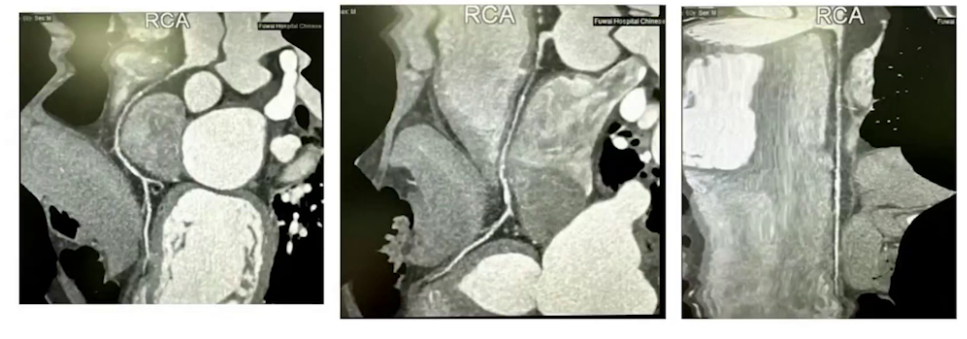

冠脉CTA+造影:右冠近端闭塞伴侧支循环形成。